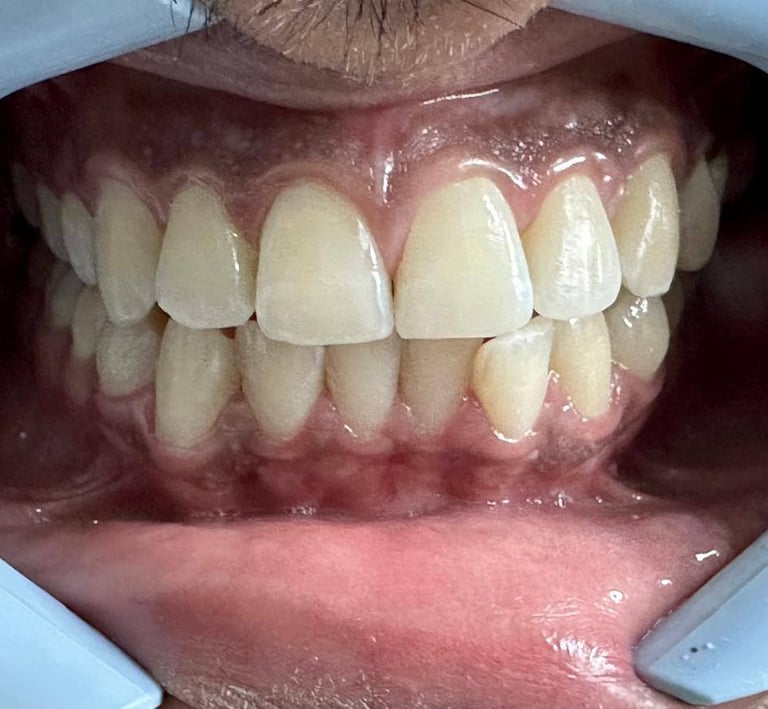

Aparelhos ortodônticos

Os aparelhos ortodônticos corrigem e

alinham os dentes. Além dos métodos

metálicos tradicionais, os aparelhos invisíveis

(como o Invisalign ) são discretos e práticos,

proporcionando um sorriso alinhado de forma

confortável e estética.